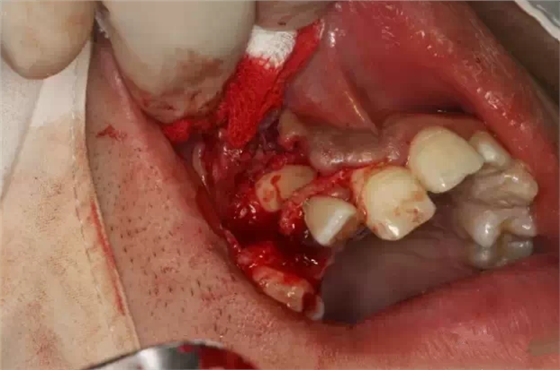

行唇側(cè)梯形瓣切開、翻瓣

骨鑿去除唇側(cè)部分皮質(zhì)骨

弧形鑿沿正畸牽引路徑去骨,作用是去皮質(zhì)骨化,保證13能順利牽引到正常位置。

高速牙鉆修整路徑外形

繼續(xù)修整

暴露13唇面

清理牙冠唇側(cè)部分軟組織